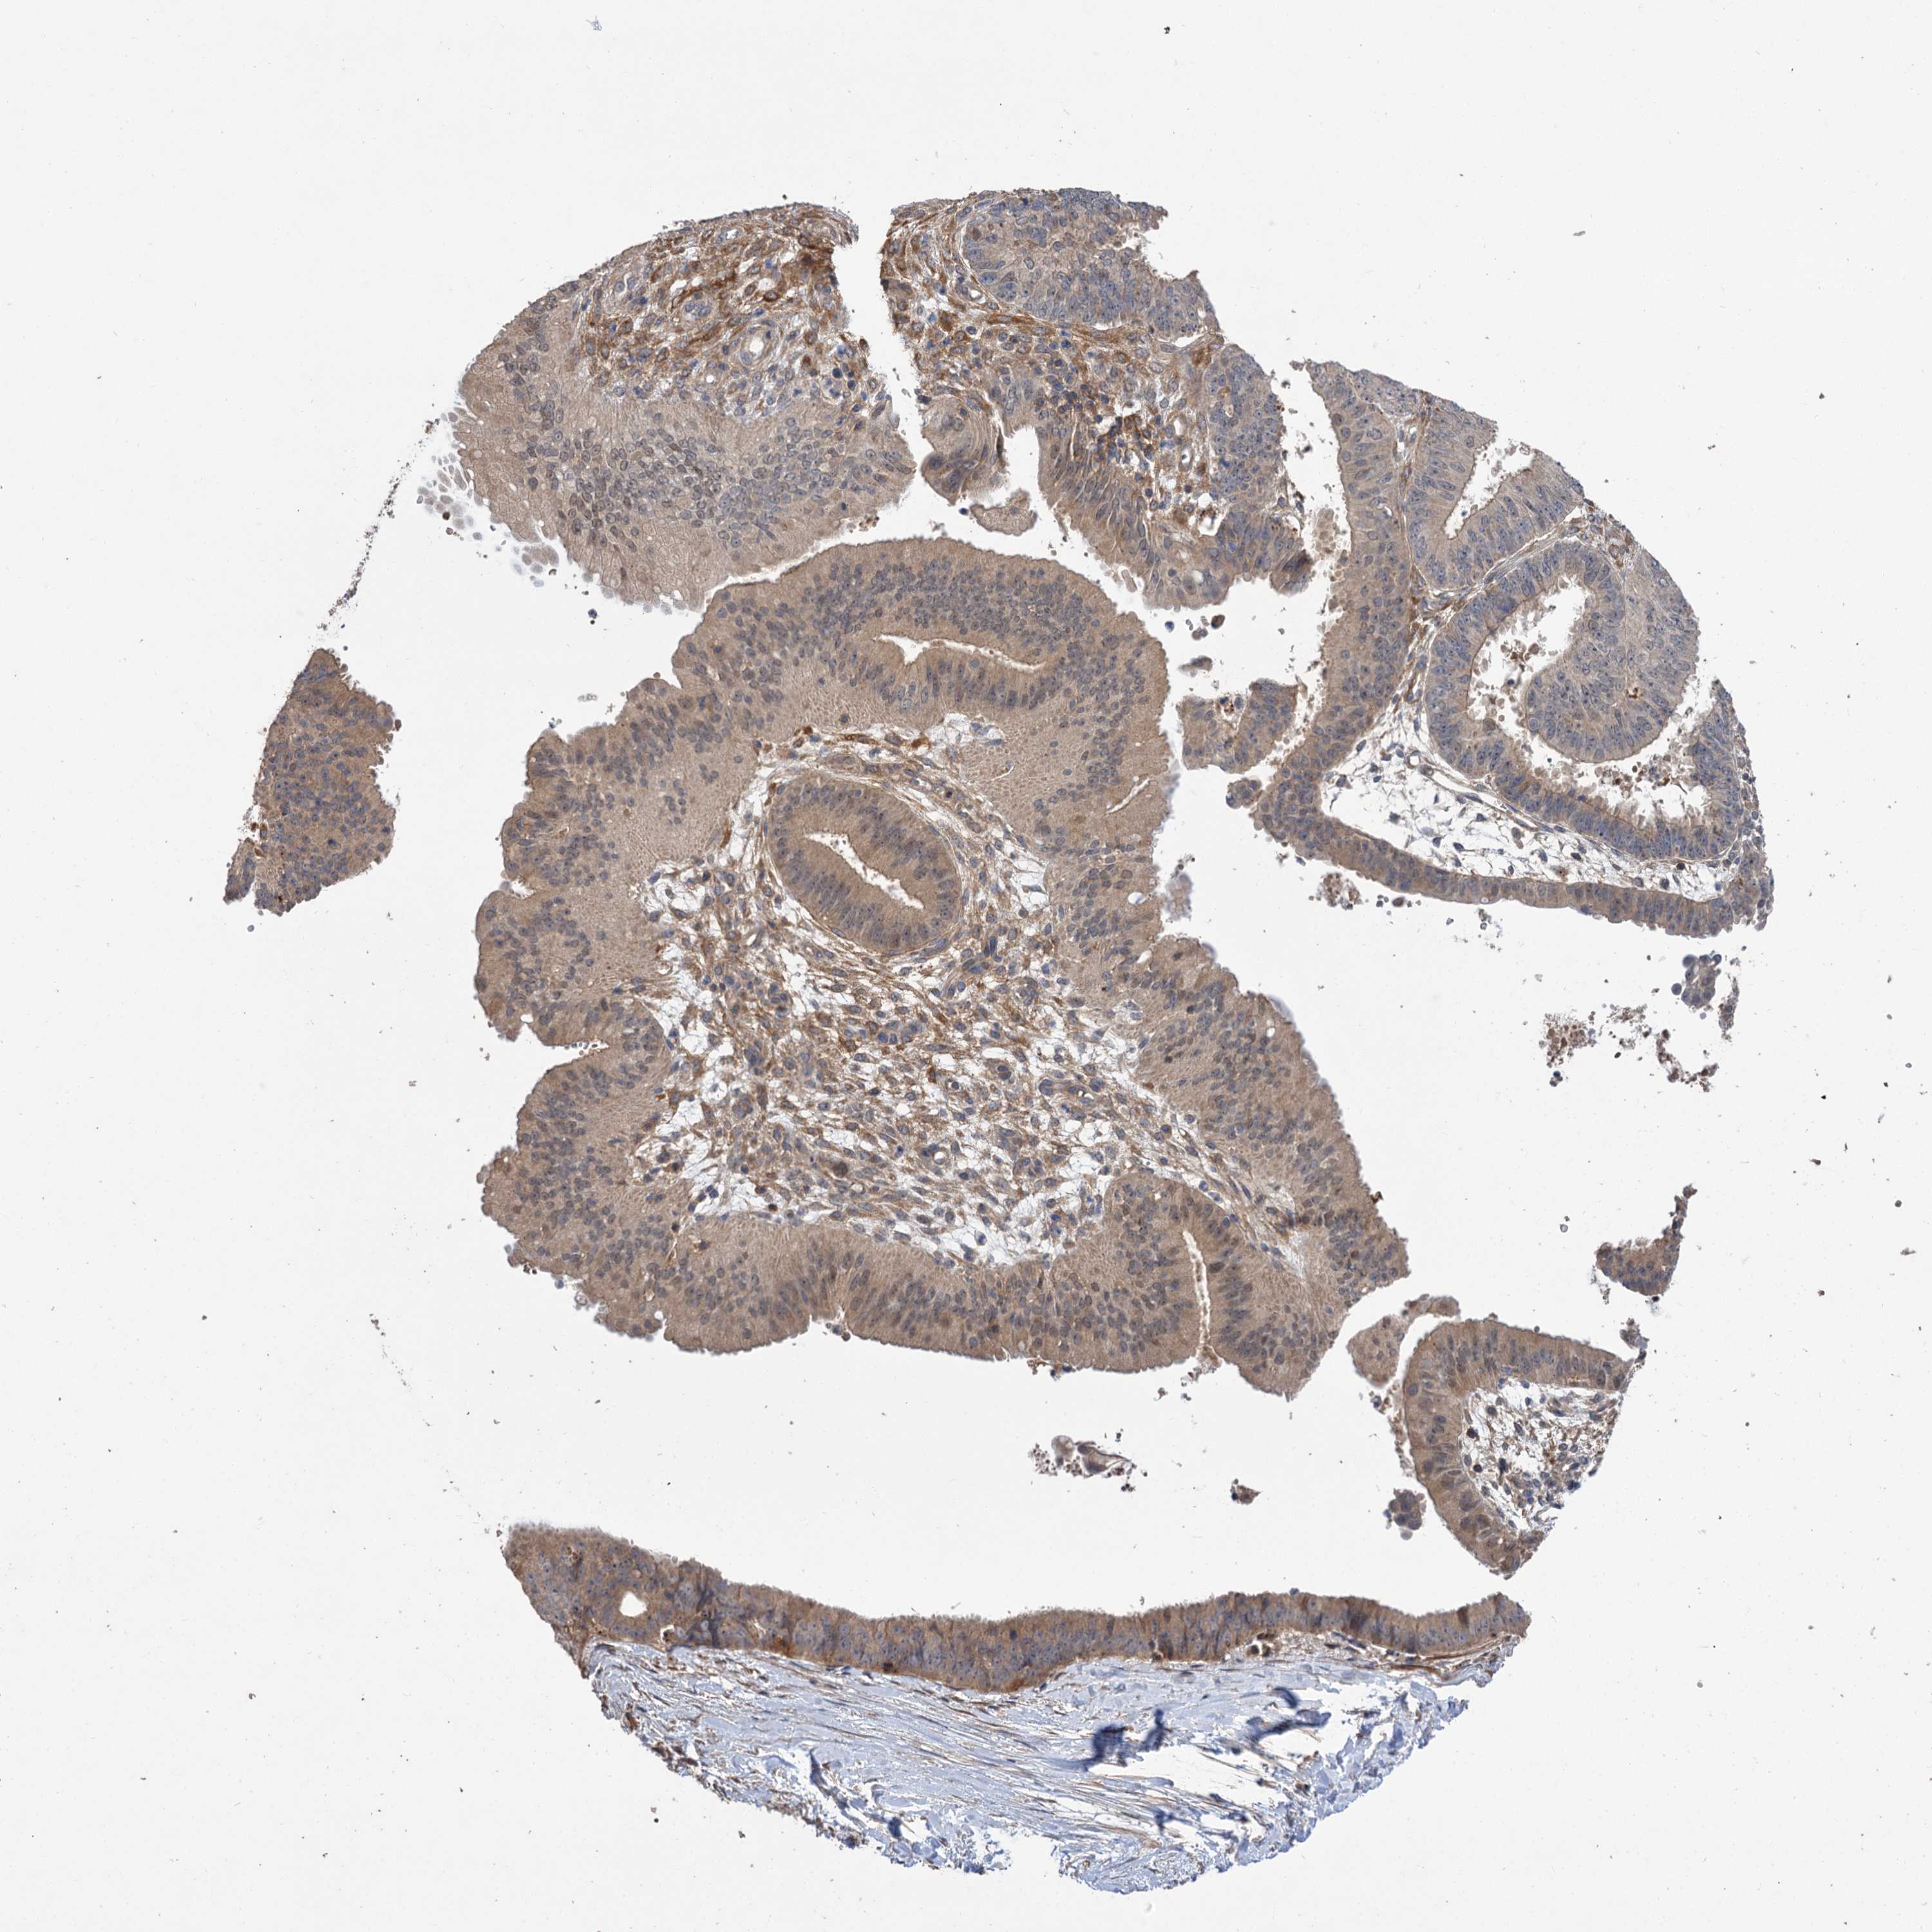

OVARIAN CANCER - Protein expressioni

A mouse-over function shows sample information and annotation data. Click on an image to view it in a full screen mode. Samples can be filtered based on level of antibody staining by selecting one or several of the following categories: high, medium, low and not detected. The assay and annotation is described here.

Note that samples used for immunohistochemistry by the Human Protein Atlas do not correspond to samples in the TCGA dataset.

Antibody stainingi

Antibody staining in the annotated cell types in the current human tissue is reported as not detected, low, medium, or high, based on conventional immunohistochemistry profiling in selected tissues. This score is based on the combination of the staining intensity and fraction of stained cells.

Each image is clickable and will lead to virtual microscopy that enables deeper exploration of all samples and also displays staining intensity scores, fraction scores and subcellular localization as well as patient and tissue information for each sample.

Antibody HPA038850

Antibody HPA038851

Cystadenocarcinoma, serous, NOS

Carcinoma, endometroid

Cystadenocarcinoma, mucinous, NOS

Carcinoma, NOS